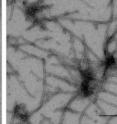

Researchers tested whether sumoylating purified alpha-synuclein hindered its clustering into fibrils, filaments similar to those detected in neurons of PD patients. If all of the alpha-synuclein molecules in a solution were sumoylated, no fibrils appeared. And even if only 10 percent of the molecules were sumoylated, fibril formation slowed dramatically.